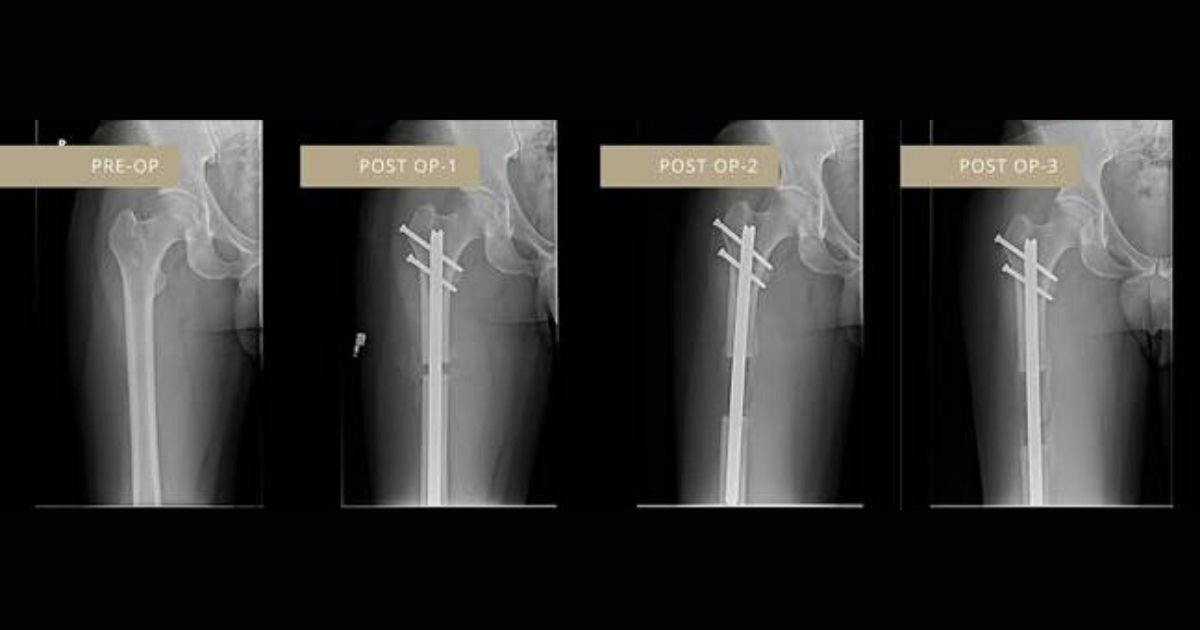

Dr. Debiparshad explained how the treatment works, he said: “Cosmetic limb-lengthening is an elective procedure where I cut the leg bones – either the femur (upper leg bone) or tibia (lower leg bone) – and insert a device that slowly stretches them out to permanently extend a person’s height.”

“It’s an X-ray based surgery where I make four to six small incisions into the leg, allowing access to the hollow part of the bone, where I insert a device that responds to an external remote control that the patient controls at home.”

“Once the device is set, I place screws at the top and bottom of the device to lock into position. This is done on each leg. Post-surgery, the external remote control is used by the patient to simply increase their height by 1mm per day at the touch of a button, slowly stretching the legs to increase their height.”

“[The results] were evident very quickly after surgery. I started using the external remote control a couple of days after the procedure and it increased my height about 1mm a day until I reached my ideal height.”